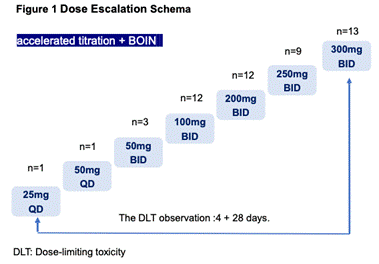

еЕ•зїДжВ£иАЕжЧҐеЊАжО•еПЧињЗжЙЛжЬѓгАБжФЊзЦЧжИЦеМЦзЦЧеМїж≤ї�����пЉМеЕґдЄ≠�����пЉМ78.4%пЉИn=40пЉЙзЪДжВ£иАЕдЄЇNSCLCжВ£иАЕ�����пЉМзФЈжАІдЄОе•≥жАІжВ£иАЕжѓФдЊЛзЫЄињС�����пЉМ21.6%пЉИN=11пЉЙзЪДжВ£иАЕеЗЇзО∞CNSиљђзІї[1]����гАВ

и°®1.жВ£иАЕеЯЇзЇњзЙєзВє